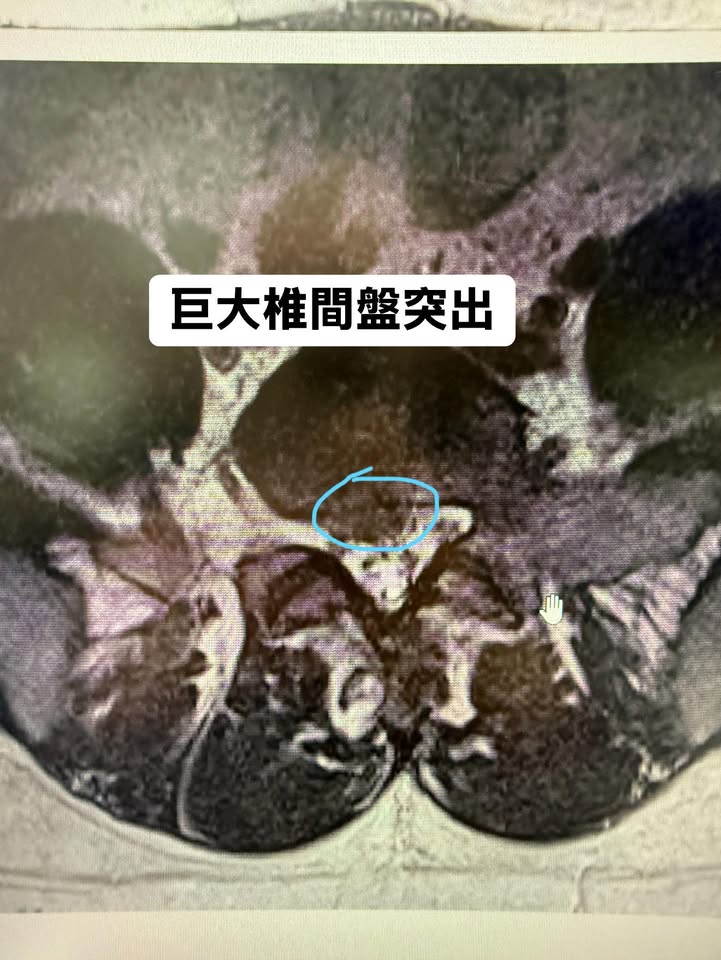

那天,她幾乎用盡全身的力氣才勉強走進我的診間。我仔細查看了她帶來的核磁共振影像,每一張切面都不放過。經過詳細分析後,我確認雖然她的椎間盤突出較為嚴重,但並未壓迫到馬尾神經,沒有大小便失禁,也沒有下肢無力等嚴重神經損害的表現。看著她略帶恐懼的眼神,我輕聲地說:「陳小姐,我知道妳現在很痛,但妳還沒到非開刀不可的地步。妳還年輕,我們可以試試非手術治療,讓妳恢復正常生活。」